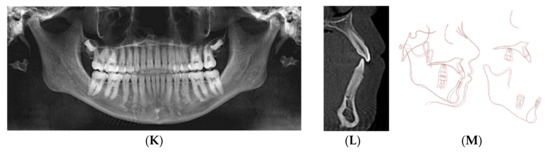

This 47-year-old male presented with chief concerns including correcting his crowded teeth (upper arch 5 mm and lower arch 4 mm arch length deficiencies), increased overjet (7 mm), and improving his recessive chin without surgical intervention, if possible. The patient was also not interested in regular fixed appliance. Clinical records (Figure 2A–E) revealed a convex profile with recessive/double chin, skeletal Class II apical base relationship (ANB = 9°) with high mandibular plane angle (FMA = 35°), and compensated upper and lower incisors (U1 NA = 6 mm; U1-SN = 98°; LI NB = 11.3 mm; L1MP −99°). Intraoral photographs and the panoramic radiograph reveal a missing upper right second molar, upper left first and second molars, and lower right first molar. In addition, both panoramic and cephalometric radiographs (Figure 2C,D) reveal a short mandibular ramus and body as well, which makes non-surgical treatment of the case more challenging. Figure 2E shows the crown-root ratio of lower incisors more than 1:1 with thin alveolar bone labio-lingually, which makes it very difficult or risky to move the lower incisors enough to minimize lower arch crowding or minimize overjet should camouflage treatment be proposed.

Figure 2.

(A) Initial photographs showing convex profile with recessive chin and anterior crowding. (B) Initial digital models showing left side Class II buccal occlusion with a 7 mm increased overjet. (C) CBCT-driven cephalometric radiograph showing convex profile with recessive chin and protrusive upper incisors. (D) CBCT panoramic radiograph showing missing 1.7, 2.6, 2.7, and 4.6 molars; no other noticeable intraoral bony lesion could be detected. (E) CBCT-driven sagittal screen of lower incisor showing its severe proclination with minimum bone appears on most of the labial surface of the root and compromised crown/root ratios. (F) Digital treatment plan (ClinCheck) showing posterior teeth intrusion to help forward rotation of the mandible palatal root torque of upper incisors. (G) Upper arch digital treatment plan (ClinCheck) showing expansion (blue—initial teeth position, white—final teeth position) and retraction of upper incisors to improve their initial protrusion. (H) Lower arch digital treatment plan (ClinCheck) showing (blue—initial teeth position, white—final teeth position) with interproximal reduction plan to allow lower incisor intrusion and leveling /alignment of lower incisor crowding. (I) Final photos showing improved patient’s profile and chin projection as well as aligned upper and lower incisors and Class I buccal occlusion on both sides. Additionally, some remaining posterior open bite due to the posterior teeth intrusion remains; the patient was happy and requested finishing by letting his posterior teeth settle through final retainers. (J) CBCT-driven final cephalometric radiograph showing improved profile and chin projection. (K) Final CBCT-driven panoramic radiograph. (L) Final CBCT-driven sagittal screen radiograph of upper and lower incisors showing improved overjet and bone labial to both upper and lower incisors. (M) Superimposition of cephalometric tracing of before (black) and after (red) treatment showing improved forward chin projection, palatal movement of upper incisors, and profile and chin projection and lingual tipping of lower incisors.

Treatment plan and progress: The patient was treatment planned using Invisalign clear aligners including upper arch expansion, posterior teeth distalization, as well as intrusion simultaneously to improve overjet and also to allow the forward/vertical bite jump to improve overjet as well as to improve the patient profile. The four digital plans for this patient (ClinCheck®) included a total of 140 aligners. Interproximal reduction (IPR) was also prescribed for this patient to minimize black triangles between front teeth as well as to move the upper and lower incisors lingually (Figure 2F–H). Upper incisor lingual movement was planned to minimize the increased overjet, and lower incisor lingual movement and intrusion were performed to minimize anterior interference after the lower jaw was to be rotated forward by posterior teeth intrusion. The patient was not very compliant with daily aligner wear (12–16 h/day) so the VPro5 HFV device was provided to him to use 5 minutes 1-3 times per day. Additionally, the patient was provided with vertical-pull chin cup (Jaw Bra, Chanhassen, MN, USA) to use every night. As a result, he was changing his aligners between 7–10 days based on his comfort with new aligners as well as the new aligners’ maximum fit to his teeth. Light Class II elastics (3/16 3.5 ounces) were provided for him to use during the day and 3/16 4.5 ounces to wear at night) so as not to interfere with his aligner wear. Total treatment time in active aligners was 24 months.

Figure 2I–M and Table 2 show posttreatment records including CBCT-driven cephalometric, panoramic, and sagittal screens of anterior teeth. The patient’s facial convexity has been improved, chief concerns (crowding and increased overjet) have been addressed. Posterior teeth uprighting in preparation of future restoration of missing teeth was achieved. In addition, posterior teeth intrusion to allow forward mandibular rotation was significant to the level it exists on the right side at the final stage. The patient was satisfied, and the slight right posterior open bite was left to settle and to be followed up during the retention phase; however, the patient did not show for follow-up during his retention period.